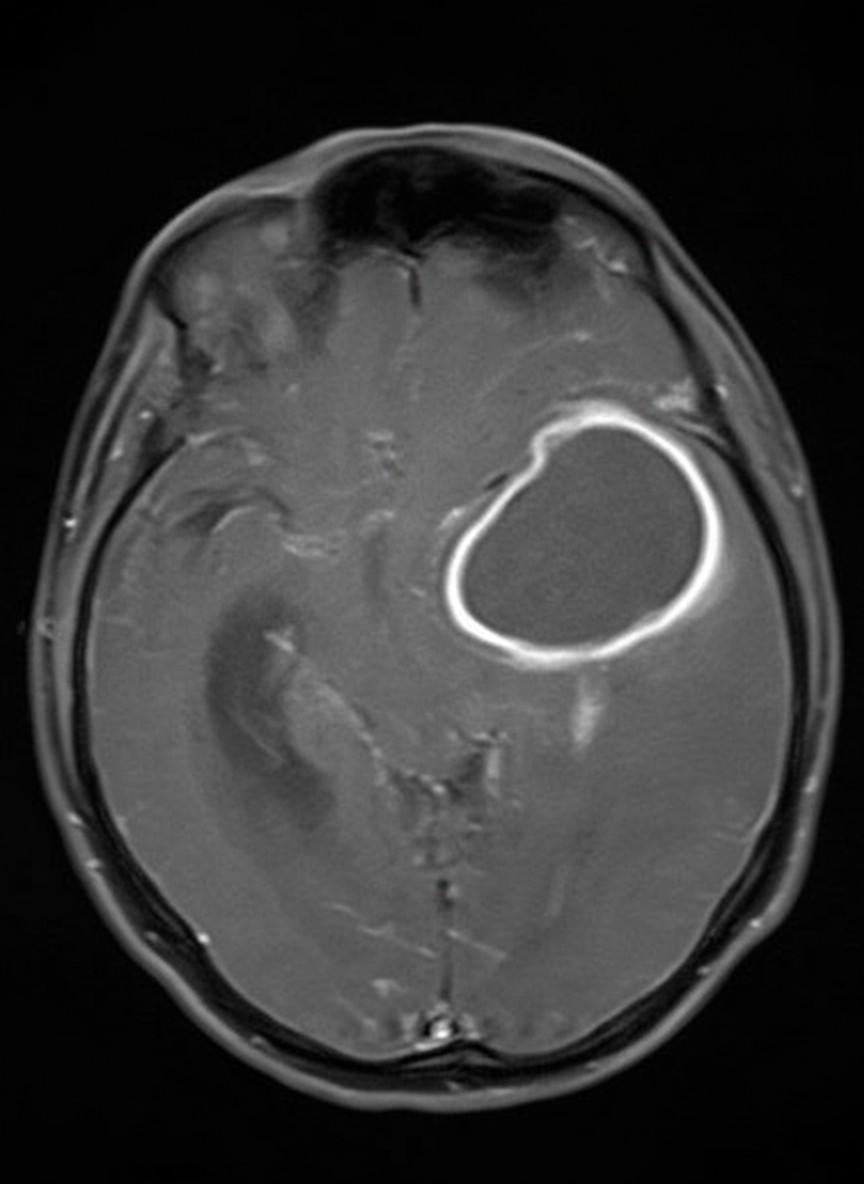

A 64-year-old man presents with headache and left-sided upper extremity weakness. The MRI of the brain is shown. What does the MRI exhibit?

Explanation: ***The lesion shows a ring pattern of enhancement with intravenous contrast and has a nonenhancing necrotic center.*** - **Ring enhancement** with **central necrosis** is the hallmark finding of high-grade malignant brain lesions like **glioblastoma multiforme (GBM)** or **brain metastases**. - The **nonenhancing necrotic center** results from rapid tumor growth outpacing blood supply, leading to central tissue death while the viable tumor periphery enhances. *The lesion is regular in shape.* - Malignant brain tumors typically demonstrate **irregular, infiltrative borders** rather than regular geometric shapes. - **High-grade gliomas** characteristically show **butterfly-shaped** or **multifocal irregular patterns** due to their aggressive growth. *The lesion is well demarcated from surrounding brain tissue.* - Malignant lesions exhibit **poorly defined margins** with **infiltrative growth** into surrounding brain parenchyma. - **Primary brain tumors** like GBM characteristically show **ill-defined borders** unlike benign lesions such as meningiomas. *The lesion shows an absence of surrounding white-matter edema.* - **Vasogenic edema** is typically prominent around malignant brain lesions due to **disrupted blood-brain barrier**. - The **mass effect** and surrounding edema contribute to clinical symptoms like headache and neurological deficits in this patient.